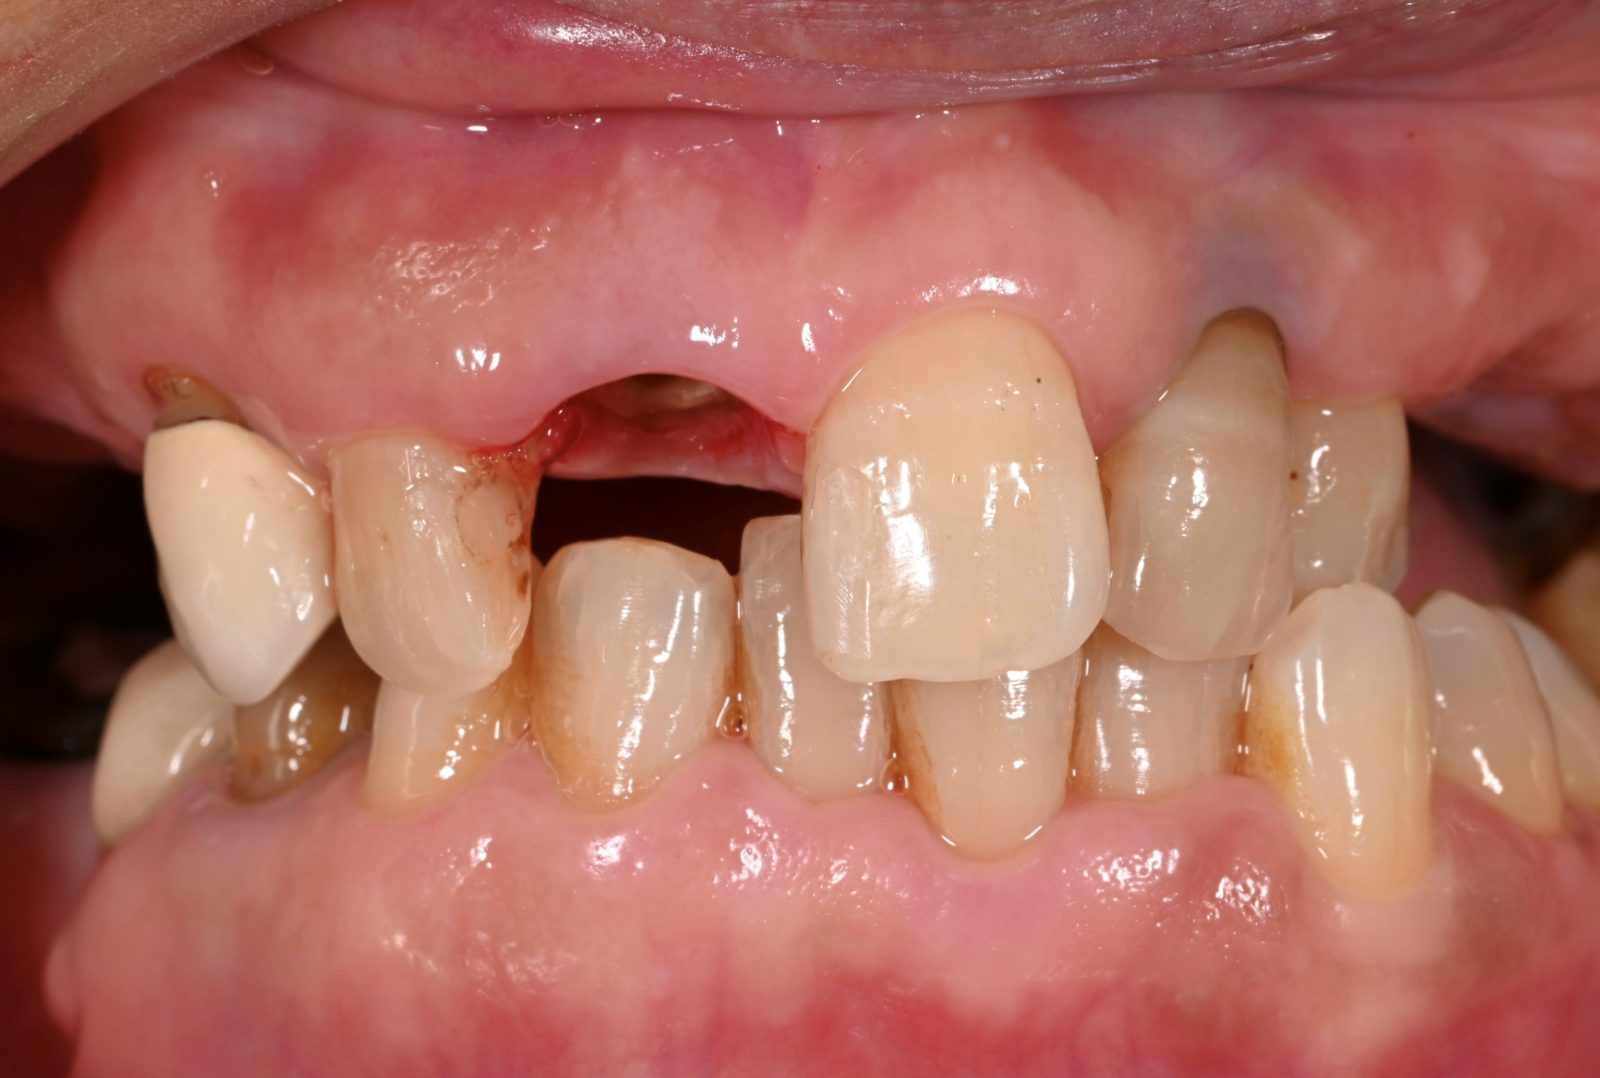

• 治療前

• 治療後